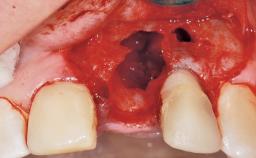

This 43-year-old male patient, a non-smoker, came to our practice because of a fracture of tooth 12 caused by a bicycle accident. Due to the combined para- and infrabony crown and root fracture, tooth extraction, and subsequent implant placement were suggested to the patient as the therapy of choice. The patient had high esthetic expectations with regard to the treatment outcome and asked for an immediate fixed provisional restoration. His individual esthetic risk profile summed up to a medium esthetic risk.

Placement Protocol Immediate implant placement

Tooth Site Maxillary incisor or canine

Socket Morphology Single-root socket

Socket Integrity Sufficient, with intact bone walls